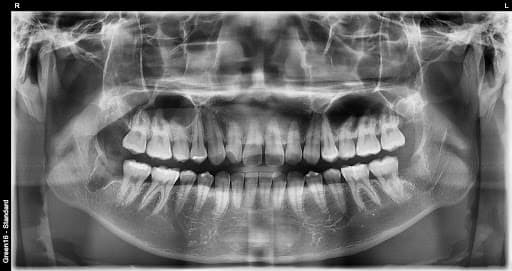

横生智齿

横向生长会挤压 相邻的牙齿

复杂的阻生智齿 - 即使深埋在牙龈中也没问题

贴近神经的智齿 - 无需担心神经损伤,安全拔除

水平阻生智齿 - 即使是横向生长的困难案例也可以处理

是的,可以。延世温雅牙科拥有丰富的拔牙经验和大学医院级别的系统来处理疑难病例。其他诊所转介到大医院的横向阻生和完全埋伏等困难病例,我们都能使用精确的3D CT诊断安全拔除。